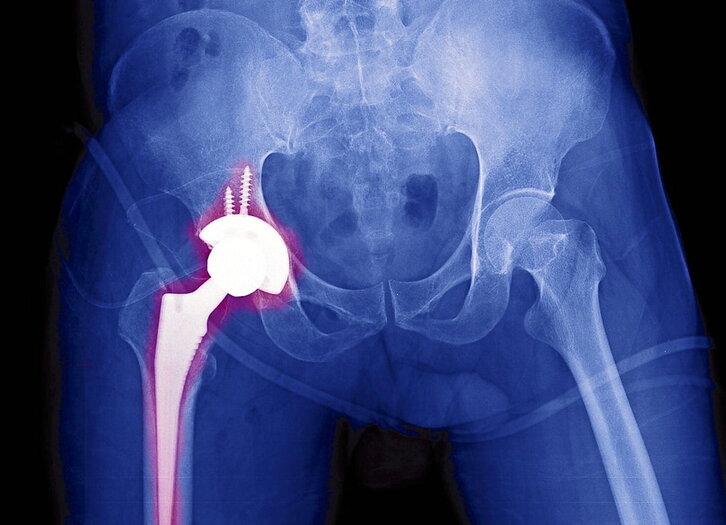

Protesi mota hauek 1960ko hamarkadan garatzen hasi ziren, batez ere John Charnley zirujau britainiarraren eraginez. Charnleyek aldakako artikulazioa ordezkatzeko metalezko eta polietilenozko piezak erabili zituen; operazioz operazio, teknika hobetuz joan zen. Hamarkada horren amaieran Frank Gunston kanadarrak belaunean aplikatu zuen, artikulazio honek duen geometria eta zinematika konplexuari aurre eginez. Protesi-interbentzioetan oraindik erabiltzen diren hainbat oinarri Charnleyek ezarritakoak dira, hala nola artikulazio-piezak hezurrari modu zurrunean finkatzea, giltzaduraren bi aldeak ordezkatzea edo higadura gutxiko materialak erabiltzea. Aldakako interbentzioak asko eboluzionatu du (batez ere protesiaren eta hezurraren arteko zimendatzea hobetuz), baina oro har egitura ez da aldatu; belauneko protesi-interbentzioek, berriz, aldaketa handiagoak izan dituzte, betiere artikulazio honen elementuen konplexutasuna berdindu nahian (konpartimentuak, kondiloak, lotailu gurutzatuak, plataforma…). Horretaz gain, artikulazio-protesietan oro har organismoaren onarpen hobea lortu da (alegia, gorputzak ez errefusatzea protesiaren elementu arrotzak), baita materialen higadura kimiko eta mekaniko gutxiago ere. Teknikoki, edozein artikulazio ordezka daiteke protesi batekin, baina praktikan, interbentzioen zatirik handiena karga gehien jasaten duten artikulazioetan izaten da (aldaka eta belauna), hauek izaten baitituzte higadura arazo handienak.